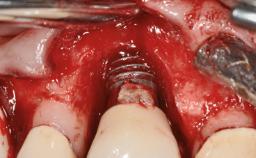

Repeated Acrylic Fractures on a Mandibular Fixed Full-arch Implant-supported Metal/Acrylic Prosthesis

A 77-year-old male patient was referred for the management of frequent and repeated acrylic fracture of his existing mandibular fixed full-arch implant-supported metal/acrylic prosthesis. He also complained about softtissue soreness and the lack of retention and stability of his maxillary removable partial metal/acrylic prosthesis. Both prostheses had been delivered two years previously as part of his full-mouth rehabilitation (caries, tooth wear, tooth fracture). His medical history revealed high blood pressure, controlled with the use of antihypertensive medication.

Type of Implants Two-Piece

Defining Characteristics Fully edentulous lower jaw to be rehabilitated with two or more implants

Modality > 4 implants, extending to mental nerve region